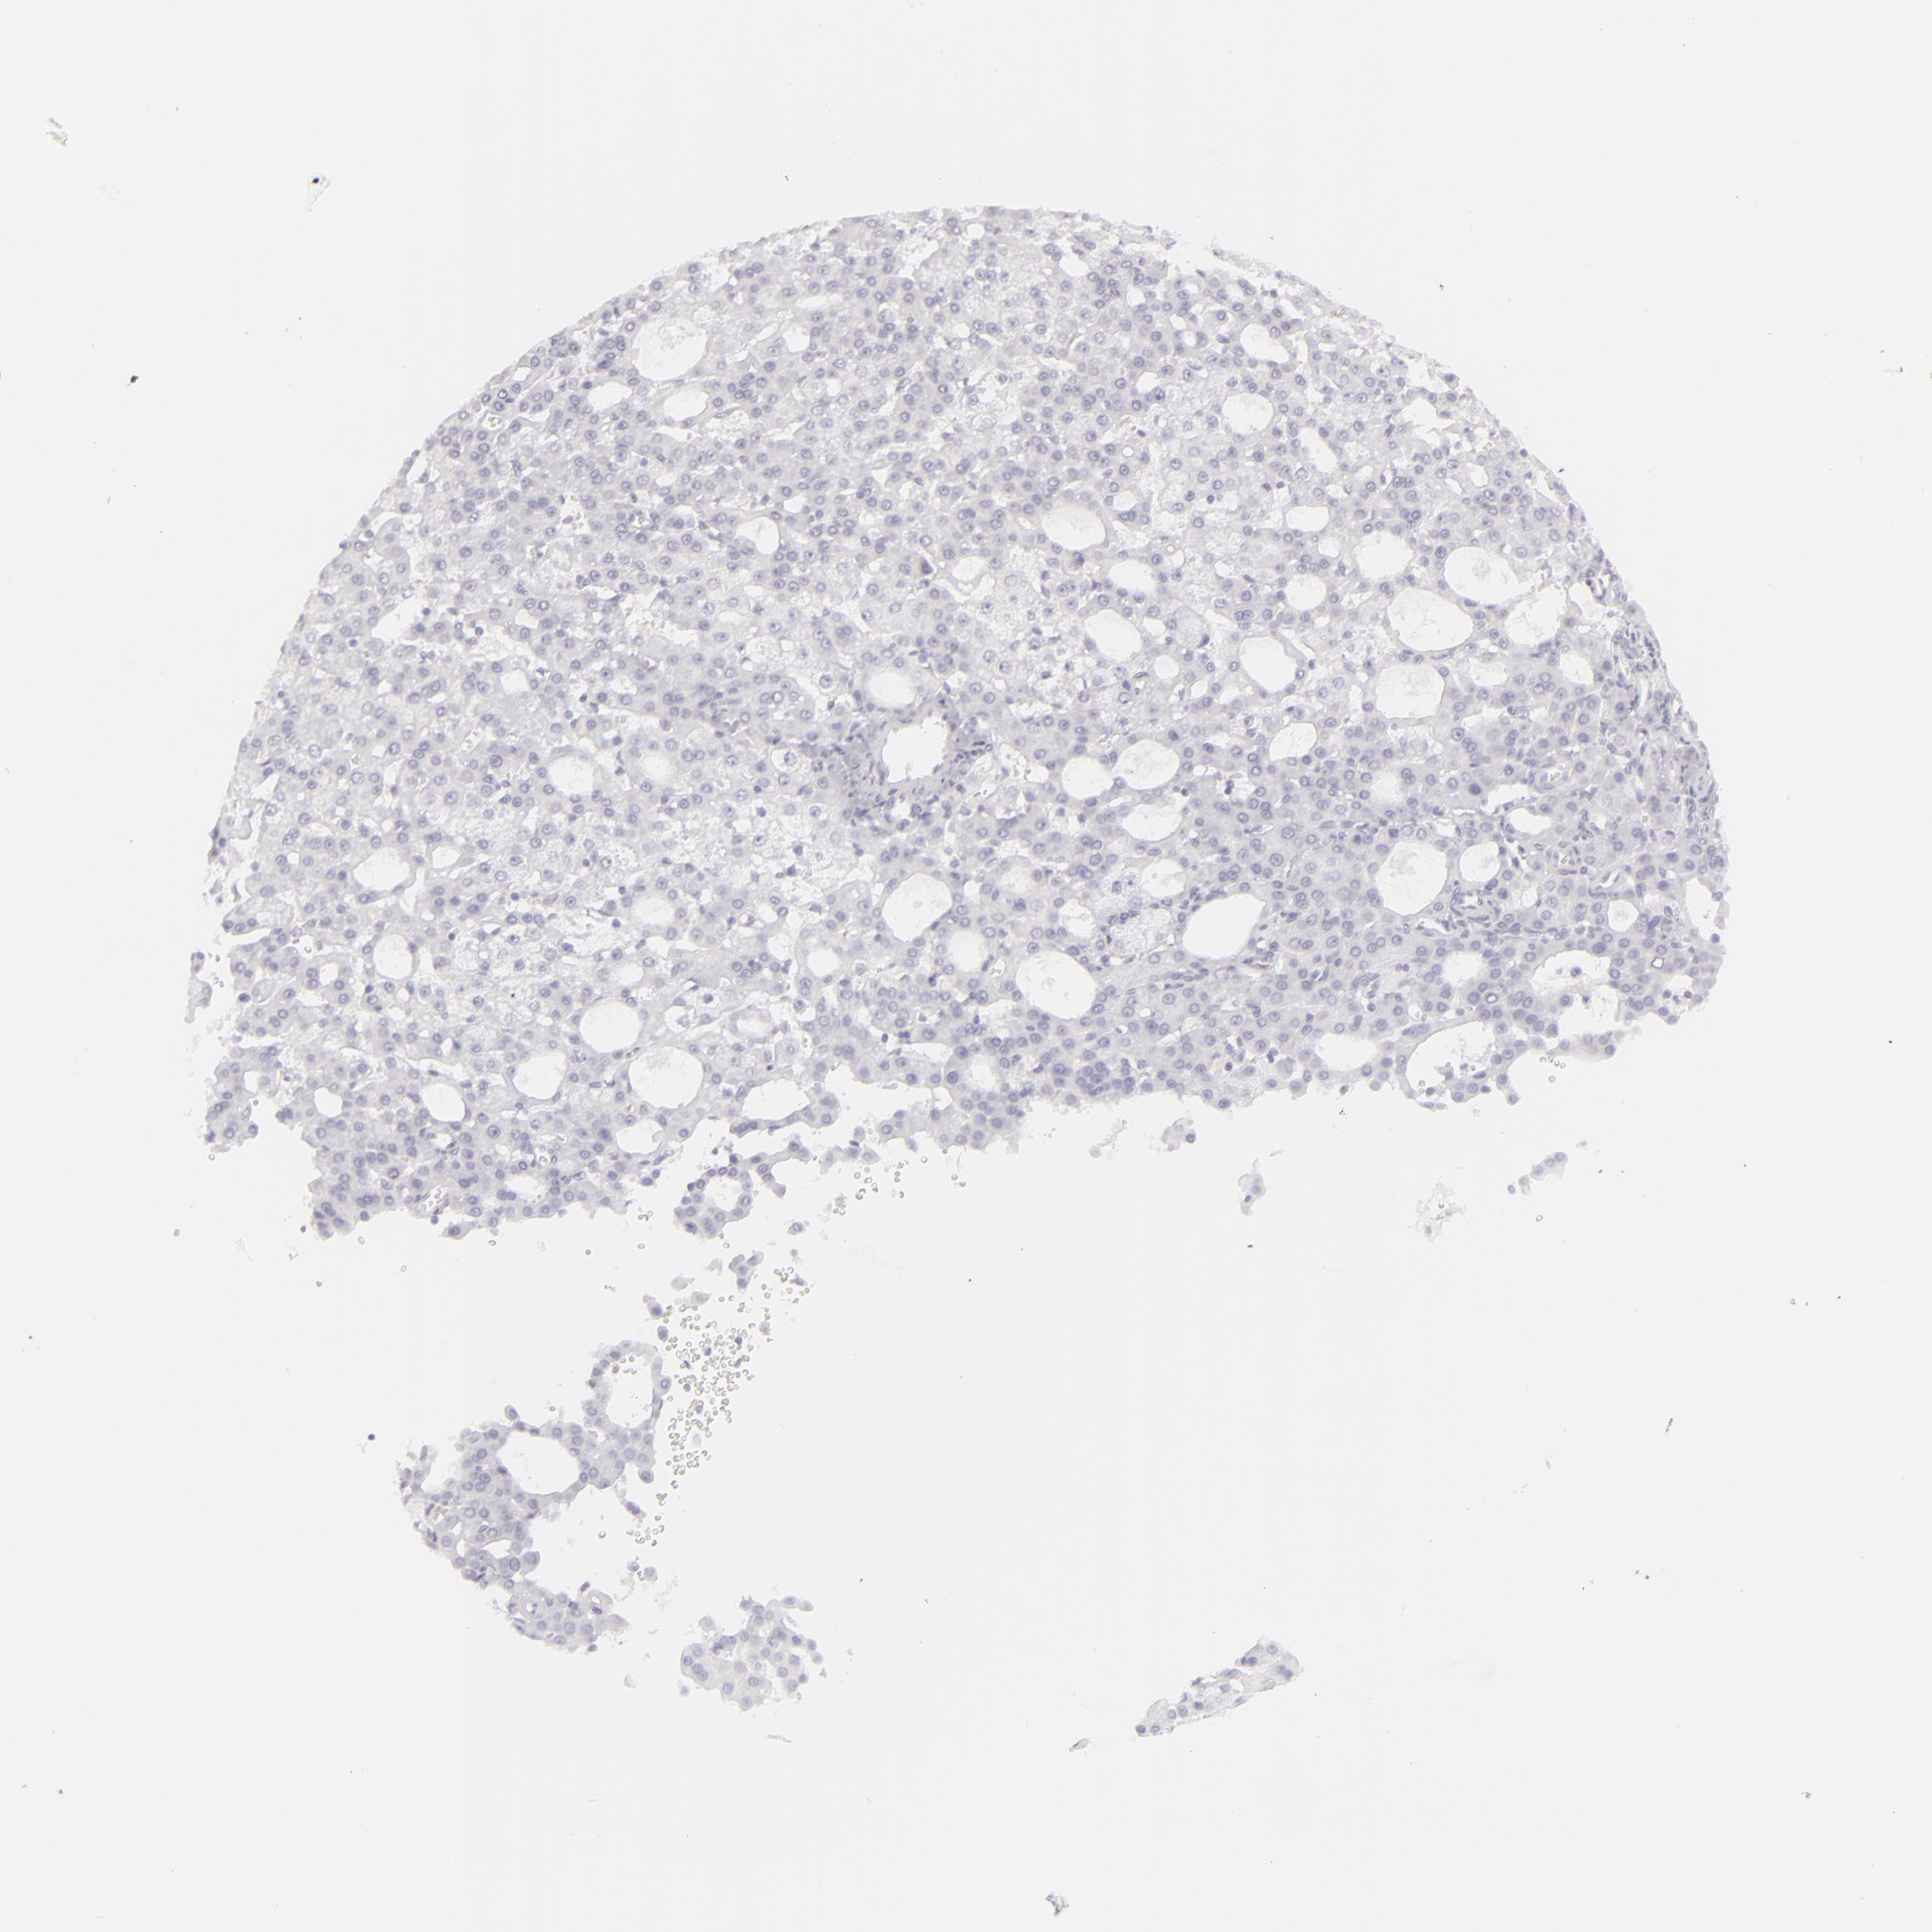

LIVER CANCER - Protein expressioni

A mouse-over function shows sample information and annotation data. Click on an image to view it in a full screen mode. Samples can be filtered based on level of antibody staining by selecting one or several of the following categories: high, medium, low and not detected. The assay and annotation is described here.

Note that samples used for immunohistochemistry by the Human Protein Atlas do not correspond to samples in the TCGA dataset.

Antibody stainingi

Antibody staining in the annotated cell types in the current human tissue is reported as not detected, low, medium, or high, based on conventional immunohistochemistry profiling in selected tissues. This score is based on the combination of the staining intensity and fraction of stained cells.

Each image is clickable and will lead to virtual microscopy that enables deeper exploration of all samples and also displays staining intensity scores, fraction scores and subcellular localization as well as patient and tissue information for each sample.

Antibody HPA030188

Antibody HPA030189

Antibody CAB002210

Cholangiocarcinoma

Carcinoma, Hepatocellular, NOS